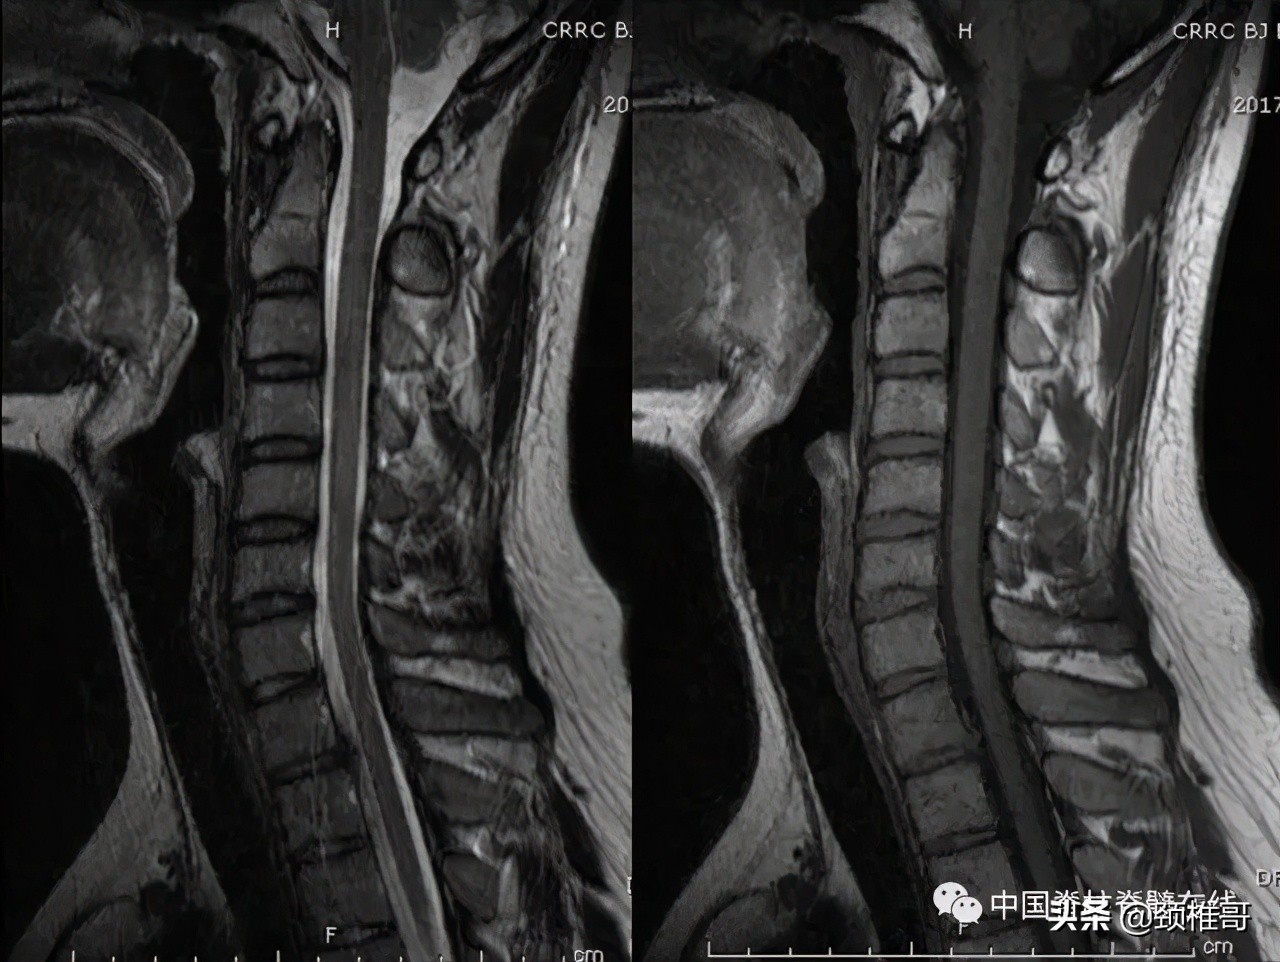

那么问题来了,大家看看这个病人,这是一位头晕2年的病人,第一位接诊大夫首当其冲给她做了一个MRI,但是椎间盘没有问题,排除颈椎病,建议到其它科室就诊;患者去了眩晕科、神经内科、耳鼻喉科、心理科、心脏内科、看过中医也看过西医,小针刀、牵引、正骨、长期颈托制动等等所有的临床治疗方法几乎全部用遍,收效甚微。还有很多像这样的患者,他们长期头晕,四处求医,甚至是求医无门。因为在核磁共振上椎间盘没有问题被排除颈椎病;因为找不到真正的病因、没有得到合理的康复而长期不愈。到我们医院之后,我让她做了很简单的颈椎动力位的片子,发现颈椎多节段明显不稳,后来就按照颈椎不稳为她制定了康复锻炼的方案,经过康复训练之后治愈。

交感神经型颈椎病患者:颈椎MRI颈椎间盘正常、颈椎生理曲度异常

颈椎正侧位:序列 欠佳 动力位:颈椎3-6各个节段之间不稳